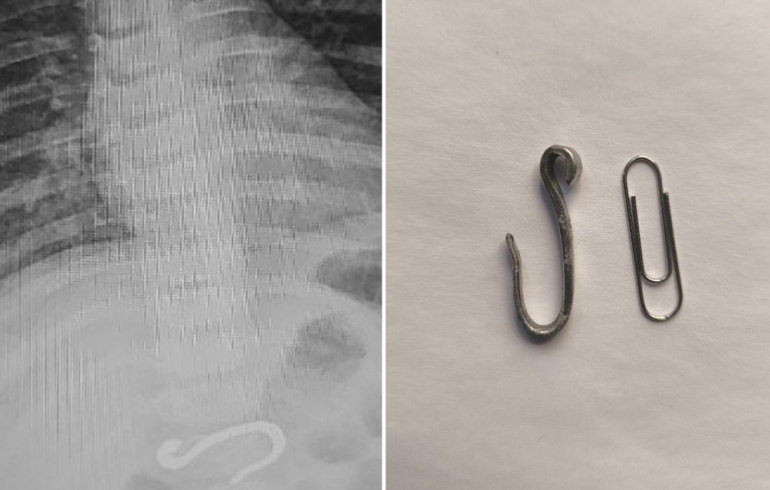

Восьмимесячный малыш поступил в приёмный покой Челябинской областной детской клинической больницы. Родители заподозрили, что младенец проглотил колпачок от ручки, но каково было удивление врачей, когда они обнаружили на снимке крупный металлический крюк. Как оказался предмет в желудке у ребёнка, понять никто не смог. А вытащить его оказалось непростой задачей.

Когда малыш попал на рентген в больнице, проглоченный крюк уже успел частично погрузиться в двенадцатиперстную кишку. Сам он был довольно внушительных размеров. Сначала доктора подумали, что крючок рыболовный, но форма и размеры предмета эту гипотезу не подтверждали. Извлечь его из организма, не повредив ткани, оказалось задачей нетривиальной. Ведь ребёнок маленький, и объём его желудка тоже небольшой.

— Мне этот крюк надо было сначала переместить из кишки в более просторное место желудка, а потом подцепить и аккуратно, не повредив ткани, извлечь наружу. Нам удалось избежать перехода на интубационный наркоз, смогли обойтись масочным, но всё заняло не менее часа, — рассказала заведующая эндоскопическим отделением Татьяна Лещёва. — Поменять позицию достаточно большого инородного тела в маленьком желудке — технически тяжело. Ширина самого крючка внушительная, намного больше, чем ребро монеты. Несколько раз на уровне пищевода крючок срывался, приходилось снова ловить, перепозиционировать, чтобы он пошёл по оси, не травмируя ткани.

В итоге всё закончилось хорошо. Металлический предмет оказался химически нейтральным, и малыша вскоре выписали домой.